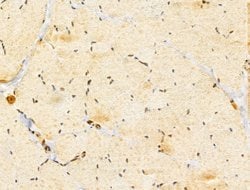

Invitrogen™ GABPB1 Polyclonal Antibody

Antibody detects endogenous levels of total GABPB1.

| Immunohistochemistry (Paraffin), Western Blot, Immunocytochemistry | |

| A synthesized peptide derived from human GABPB1(Accession Q06547), corresponding to amino acid residues V264-D314. | |

| Human, Mouse, Rat | |